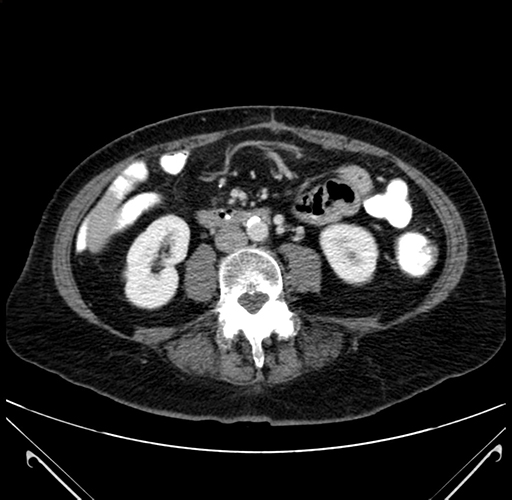

Axial Venous